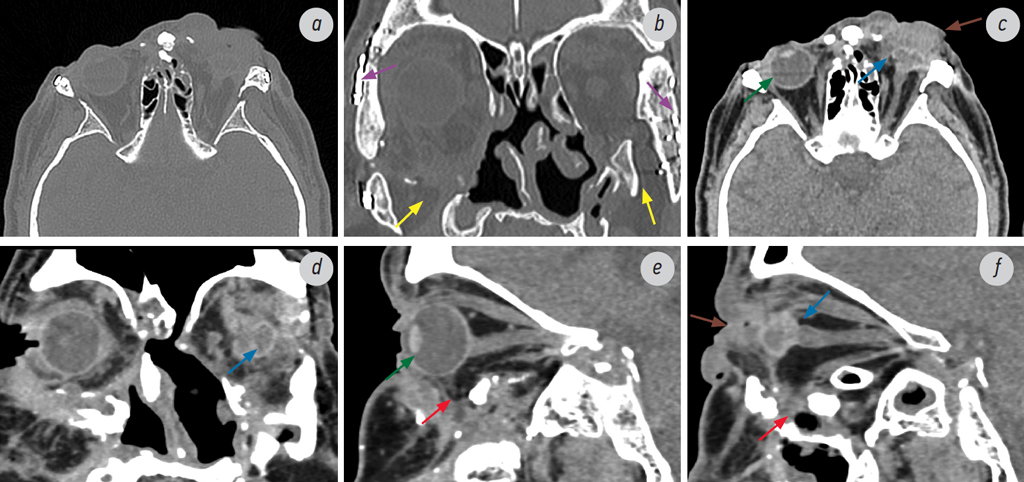

Рис. 2. Мультиспиральная компьютерная томография. Состояние перед планируемым эндопротезированием левой орбиты: а — аксиальный срез, режим костного окна; b — корональный срез, режим костного окна; c — аксиальный срез, режим мягкотканного окна; d — корональный срез, режим мягкотканного окна; e, f — сагиттальный срез, режим мягкотканного окна. Визуализируются выраженные посттравматические деформации костей средней зоны лица, переломы всех стенок орбит (кроме верхних). В связи с тотальными переломами нижних стенок орбит (жёлтые стрелки), мягкотканное содержимое орбит пролабирует книзу в полость верхнечелюстных синусов (красные стрелки). Состояние после энуклеации левого глазного яблока: в полости левой орбиты определяется остаточная ткань глазного яблока (склера) для дальнейшего формирования опорно-двигательной культи (синяя стрелка). В области обеих скуловых костей и скулолобных швов определяются элементы металлоостеосинтеза (фиолетовая стрелка). Правое глазное яблоко сохранно, с округлыми чёткими контурами, неизменённой формы, хрусталик визуализируется (зелёная стрелка). Отмечаются выраженные посттравматические деформации мягких тканей лица, в области периорбитальных тканей слева определяется увеличение объёма и уплотнение тканей (коричневая стрелка)

Fig. 2. MSCT. Condition before the planned endoprosthetics of the left orbit: a — axial slice, bone window mode; b — coronal slice, bone window mode; c — axial slice, soft tissue window mode; d — coronal slice, soft tissue window mode; e, f — sagittal slice, soft tissue window mode. Severe post-traumatic deformations of the bones of the face middle zone and fractures of all orbital walls (except the upper ones) are visualized. Due to total fractures of the lower orbital walls (yellow arrows), the soft tissue contents of the orbits prolapse into the cavity of the maxillary sinuses (red arrows). Condition after enucleation of the left globe: residual tissue of the globe (sclera) is determined in the cavity of the left orbit for further formation of the musculoskeletal stump (blue arrow). In the area of both zygomatic bones and zygomatic-frontal sutures, elements of metal osteosynthesis are identified (purple arrow). The right globe is intact, with rounded clear contours, unchanged shape, the lens is visualized (green arrow). Severe post-traumatic deformations of the facial soft tissues are noted; in the area of the periorbital tissues on the left, an increase in volume and thickening of the tissues are detected (brown arrow)